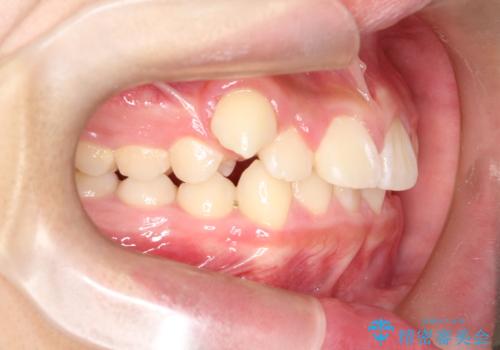

八重歯・歯並びのデコボコとディープバイトを改善した抜歯ワイヤー矯正症例

- 八重歯と咬み合わせを治したいを主訴にご来院された患者様です。

矯正の精密検査の結果上顎左右4番の計2本を抜歯し、審美性に配慮したワイヤー矯正装置(審美装置)を用いて治療を行いました。

八重歯などの歯列のデコボコが綺麗に改善され、患者様にも大変喜んでいただけました。また、咬み合わせが深い「ディープバイト」も併せて改善し、見た目だけでなく機能面でもバランスの取れた咬合を獲得しています。